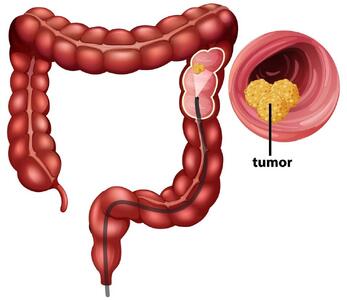

آسپرین و کاهش خطر عود سرطان

مطالعهای جدید نشان میدهد که مصرف روزانه آسپرین میتواند خطر بازگشت سرطان روده را تا ۵۵ درصد کاهش دهد، بهویژه در بیمارانی که دارای جهش در ژن PI3K هستند.

علائم ابتلا به سرطان روده بزرگ/سن مناسب انجام کولونوسکوپی - تسنیم

دکتر سیدامیرپاشا طبائیان، فوق تخصص بیماریهای گوارش و کبد بزرگسالان با اشاره به علائم ابتلا به سرطان روده بزرگ، درباره درمان و تشخیص این بیماری و سن مناسب انجام کولونوسکوپی توضیحاتی ارائه کرد.

پیش بینی احتمال ابتلا به سرطان روده

پزشکان میگویند سن بیولوژیکی که معیاری برای وضعیت فیزیولوژیکی بدن است میتواند پیشبینی کند چه کسانی بیشتر در معرض خطر ابتلا به پولیپ روده بزرگ هستند.